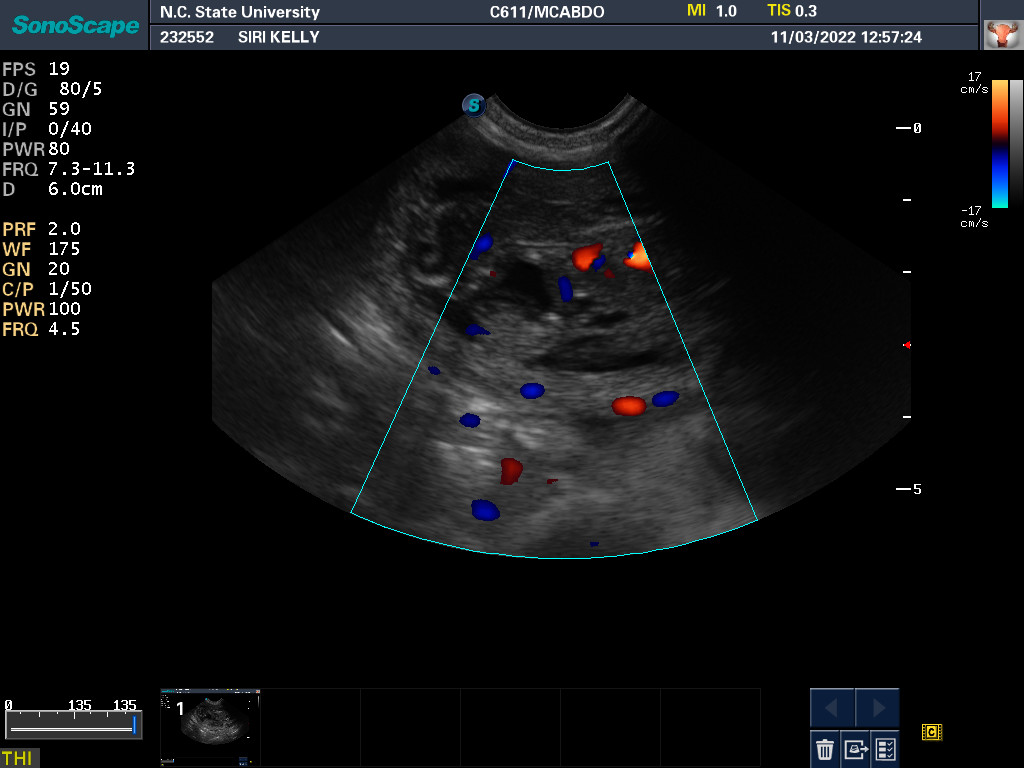

3 Nov 2022

Ultrasound today by the theriogenology (reproduction) veterinarians at NC State University showed that Siri is pregnant with possibly two puppies. It is difficult to accurately count puppies using ultrasound.

If all goes well, puppies are due around 28 November.